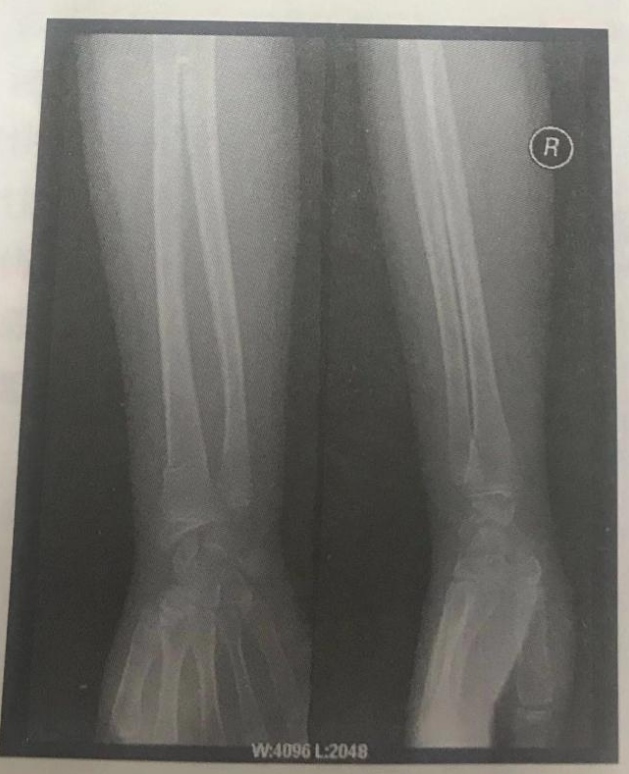

根据下面X线片判断临床意义。(5分)

右挠骨远端青枝骨折

【该题针对“ X线片”知识点进行考核】